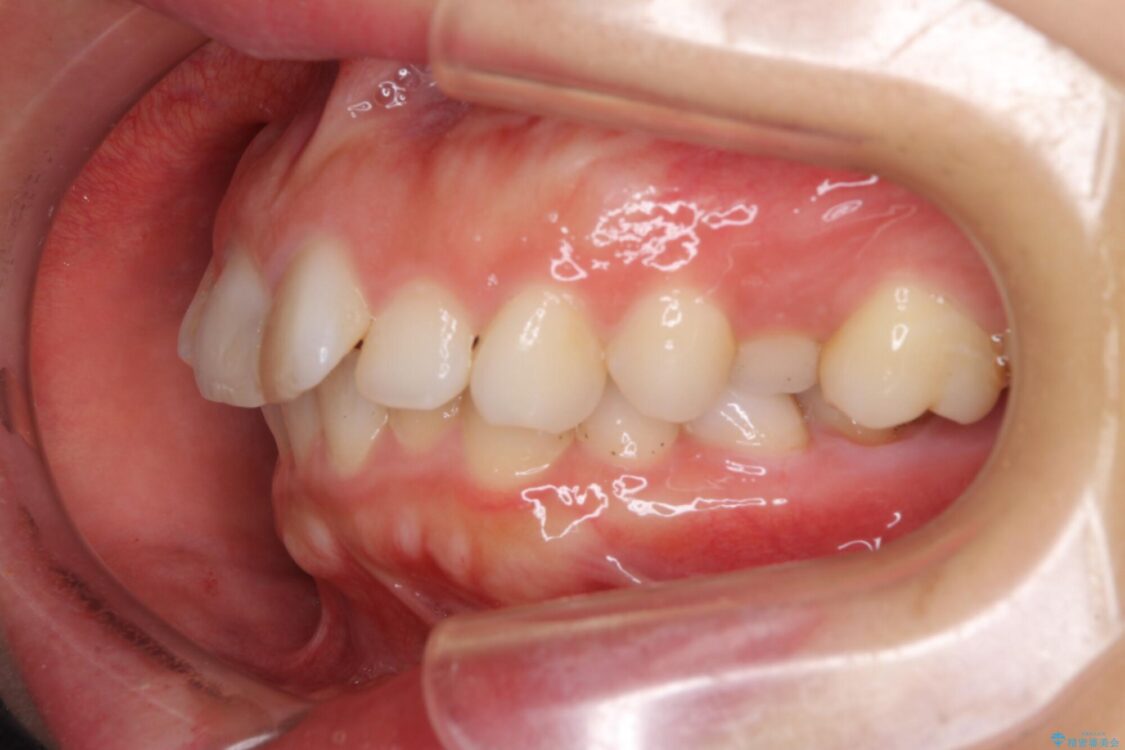

口元の閉じにくさと、奥歯の咬み合わせを気にして来院された患者様です。

左下の大臼歯2本が顕著に舌側に傾斜しているため、まずは奥歯の咬み合わせを改善をし、その後上下左右の第1小臼歯4本を抜歯することで口元を引っ込めながら整えることとしました。

治療前

• 【モニター】出っ歯と咬み合わせを改善 ワイヤー装置の抜歯矯正 治療前画像